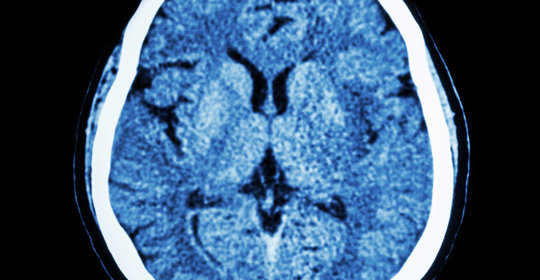

腦白質萎縮:認識腦部病變,守護大腦健康

橋腦出血:突發症狀、治療攻略一覽

丘腦出血:瞭解出血病因與科學治療